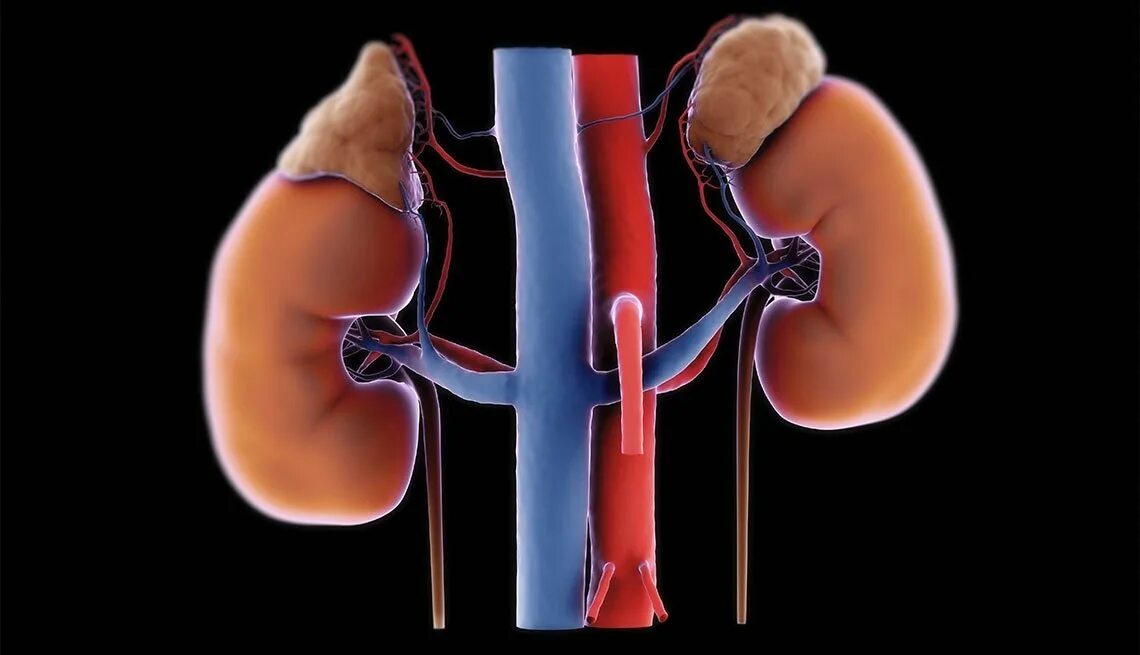

Надпочечники у собаки